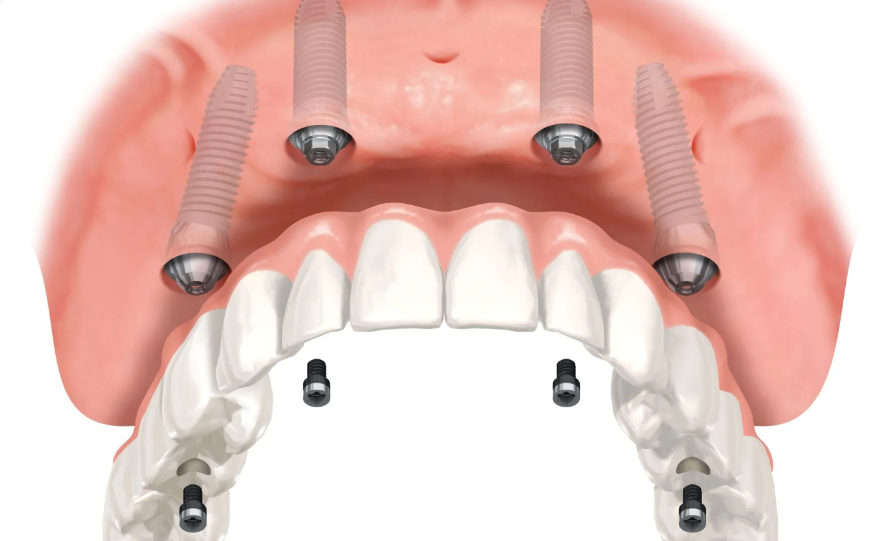

나사로 고정 식이라 넣었다 뺐다 하지 않아요.

자기 치아처럼 갈비도 뜯고

깍두기도 드실 수 있습니다.